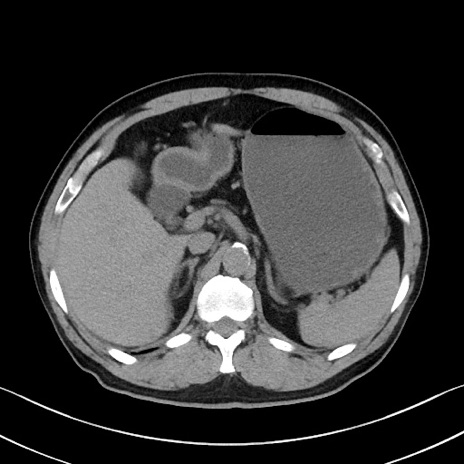

症例35(横断像)

【症例】70歳代 男性

【主訴】腹部膨満、嘔吐

【現病歴】昨日より腹部膨満感出現。本日増悪し、仙痛出現。嘔吐あり、受診。

【既往歴】糖尿病、胆摘後

【身体所見】BP 149/80mmHg、HR 74/min、BT 35.9℃、腹部:膨満、軟、圧痛なし。腸雑音減弱あり。上腹部正中切開瘢痕あり。

【データ】WBC 13500、CRP 1.72